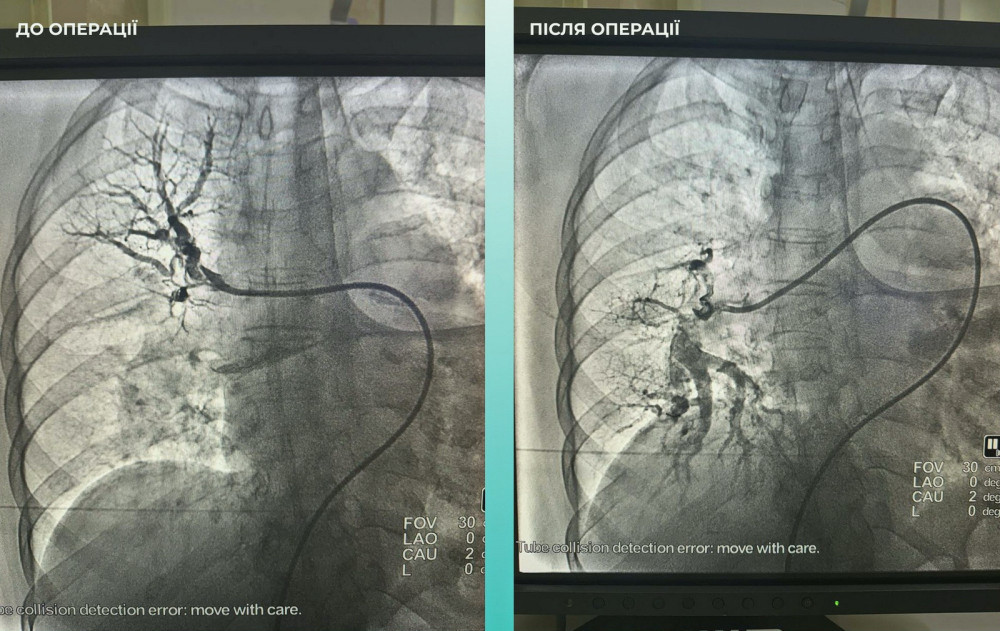

Пациентка поступила в больницу с тяжелым острым инсультом. При проведении компьютерной томографии врачи обнаружили закупорку средней мозговой артерии.

Кроме того, врачи заметили, что пациентка испытывает трудности с дыханием, поэтому провели дополнительное обследование легких. Установлен диагноз тромбоэмболии легочной артерии.

Мультидисциплинарная команда врачей приняла решение провести одновременную тромбоэктомию на мозговых и легочных артериях, что стало критически важным шагом к спасению жизни.